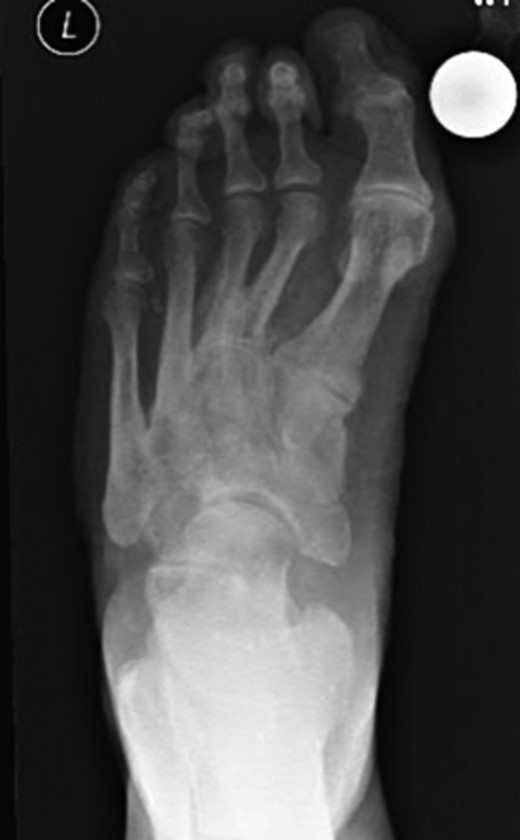

Dorsoplanter, lateral and oblique radiographs demonstrated an additional bone immediately distal to the middle cuneiform articulating with the second metatarsal base and middle cuneiform. Second and third metatarsals were shorßt in comparison with normal (Figs 1–3). Osteoarthritis was seen in all TMTJs and the first MTPJ. A computed tomography (CT) scan confirmed the presence of the additional bone and degenerative joint disease (Figs 4 and 5).

Lateral radiograph of the left foot with the clearly visible additional middle cuneiform.